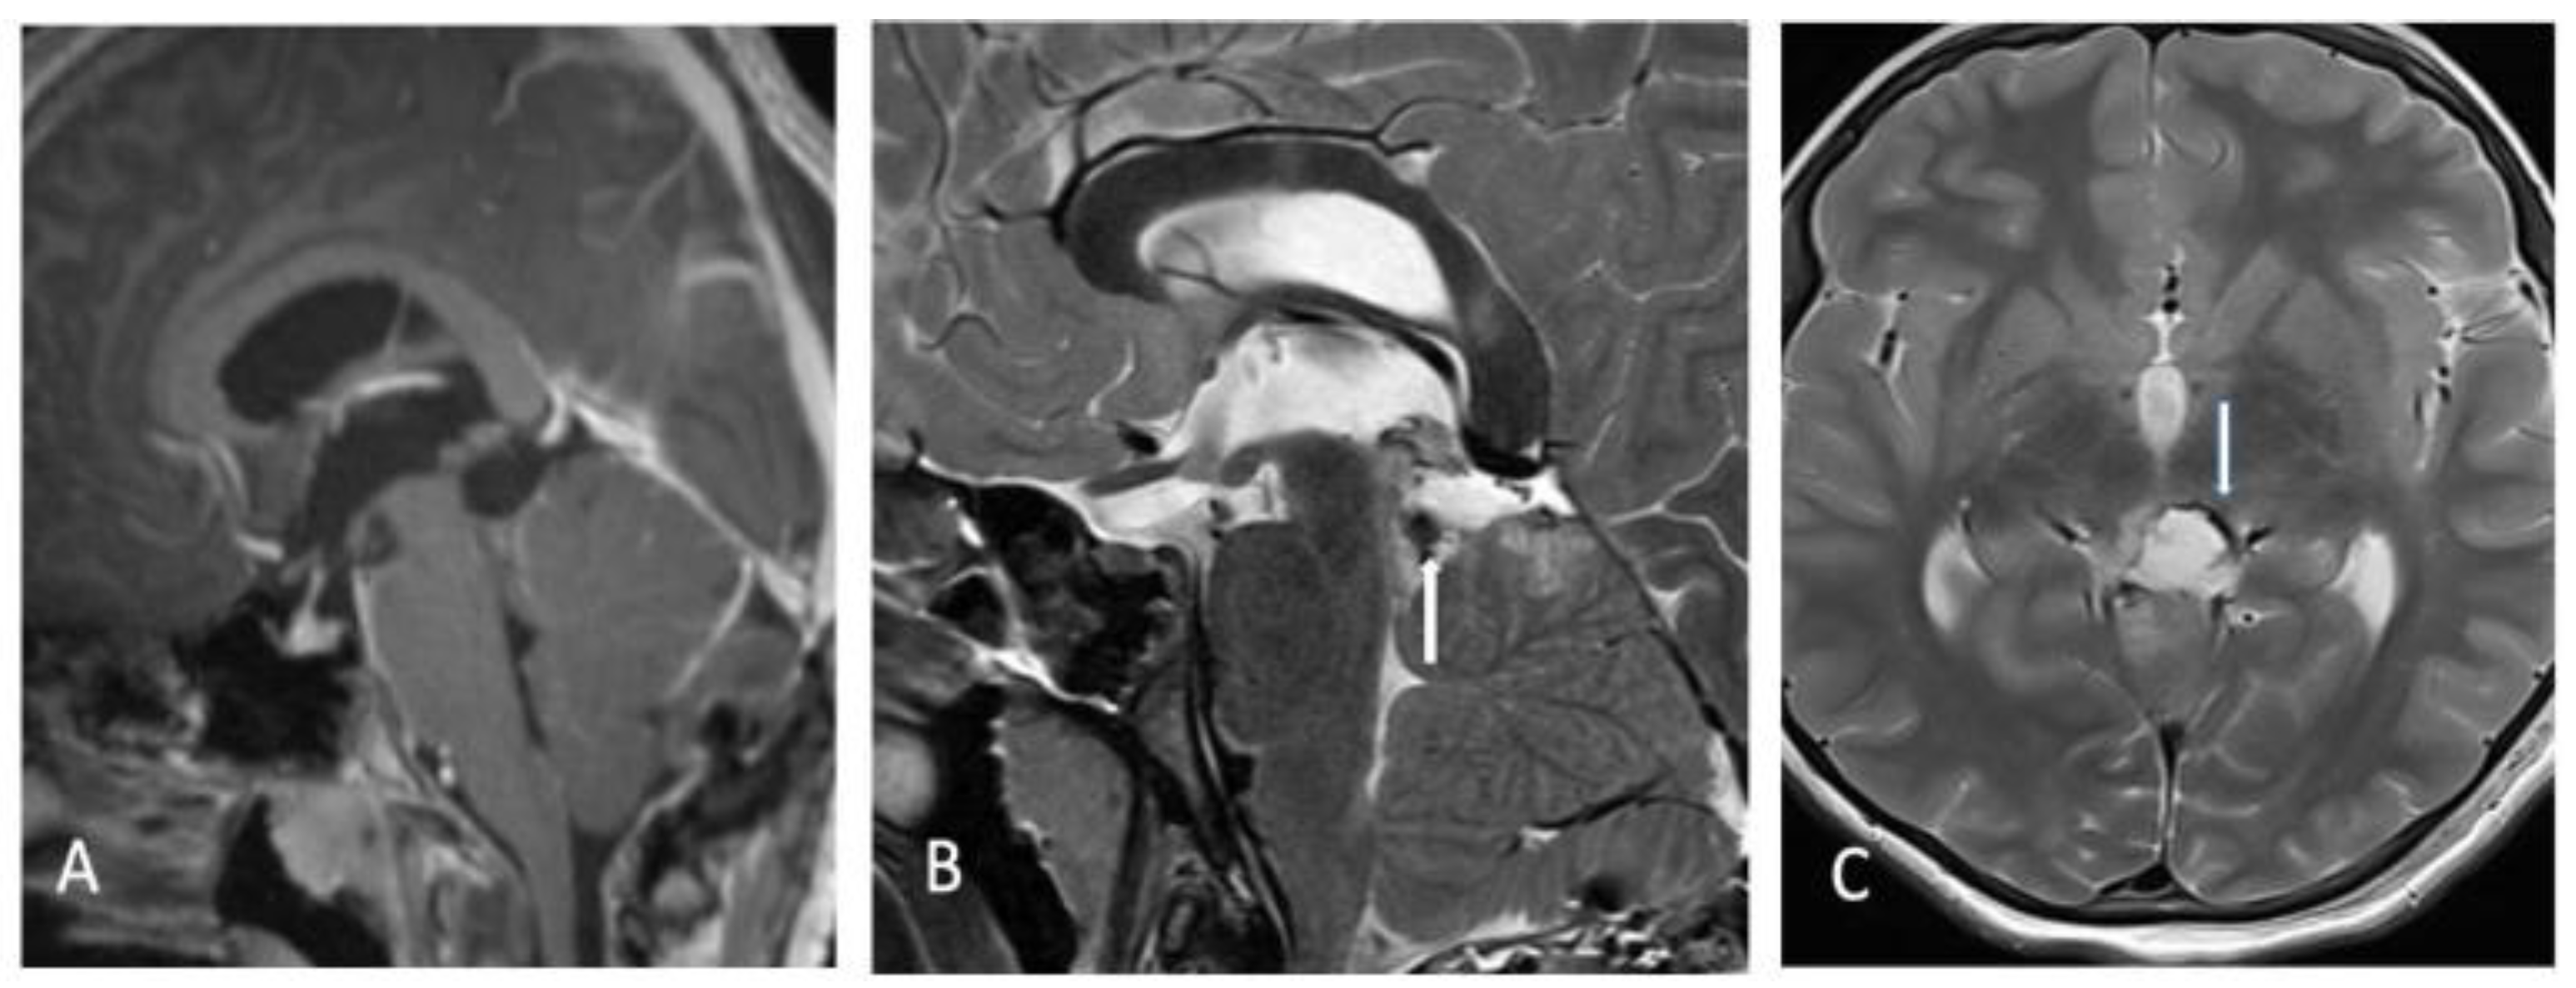

3. Operative Technique